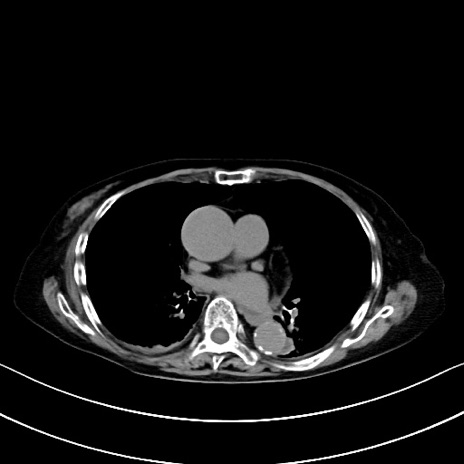

症例40(横断像)他院1日前

横断像

他院CT